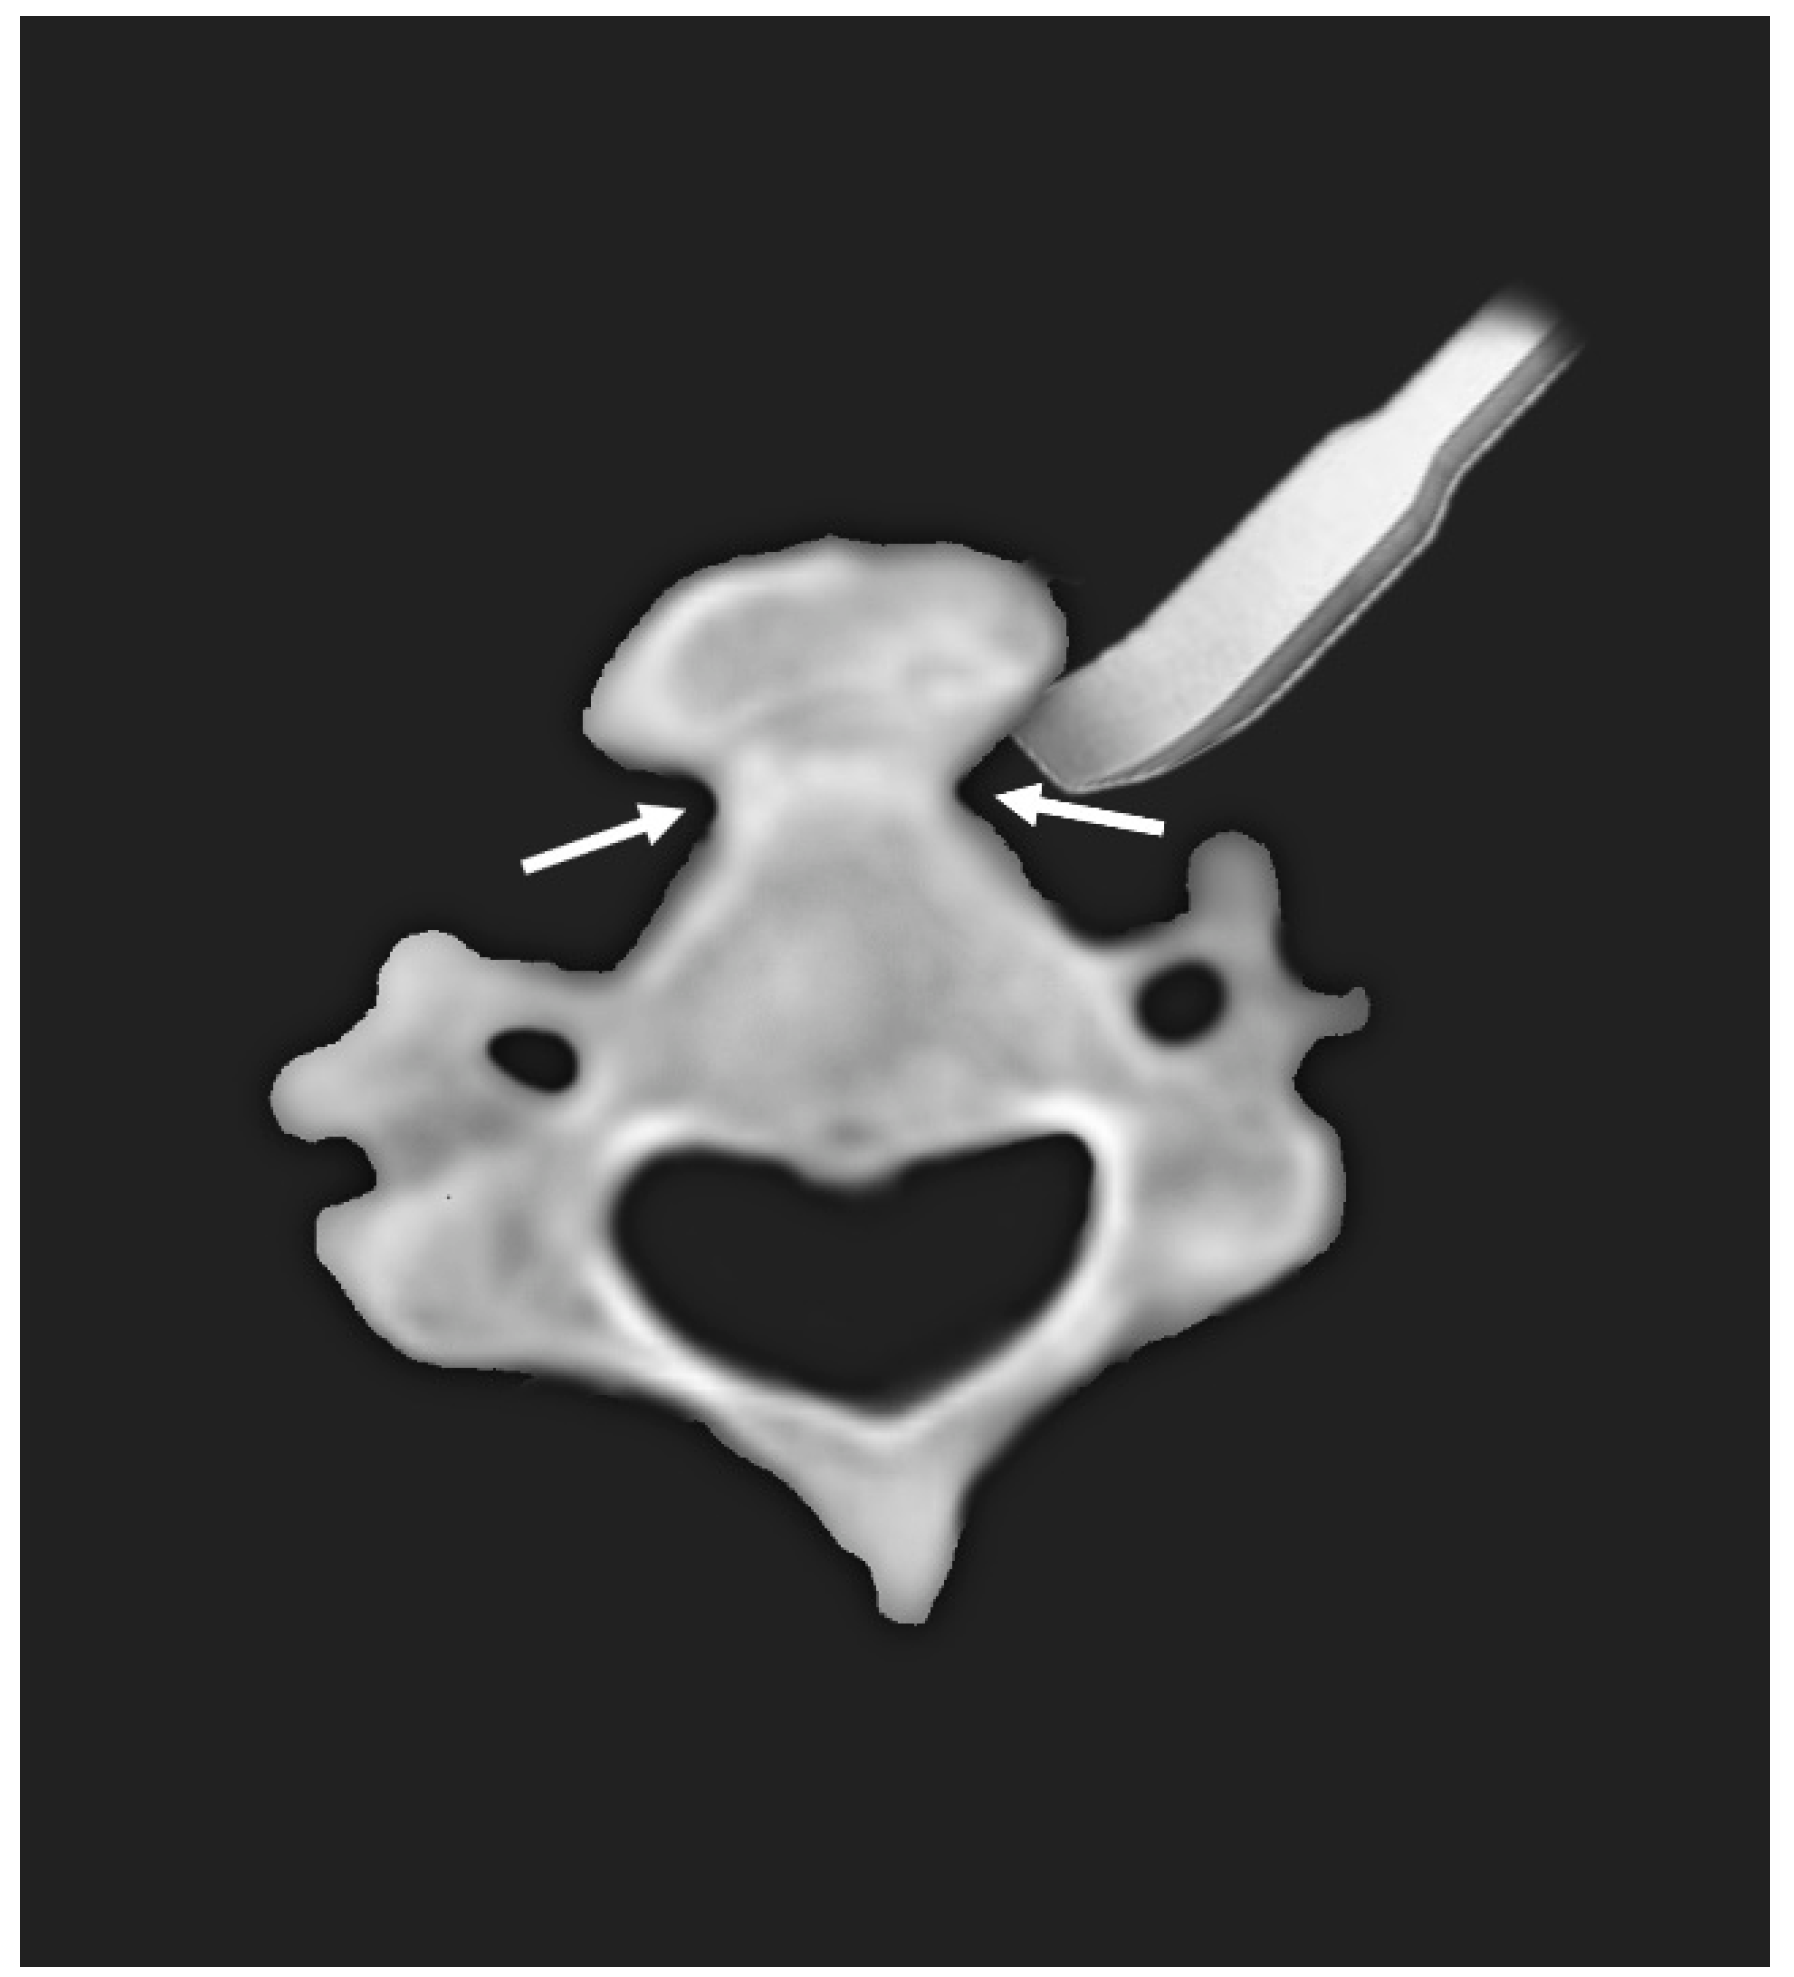

2.1. Case 1

2.2. Case 2